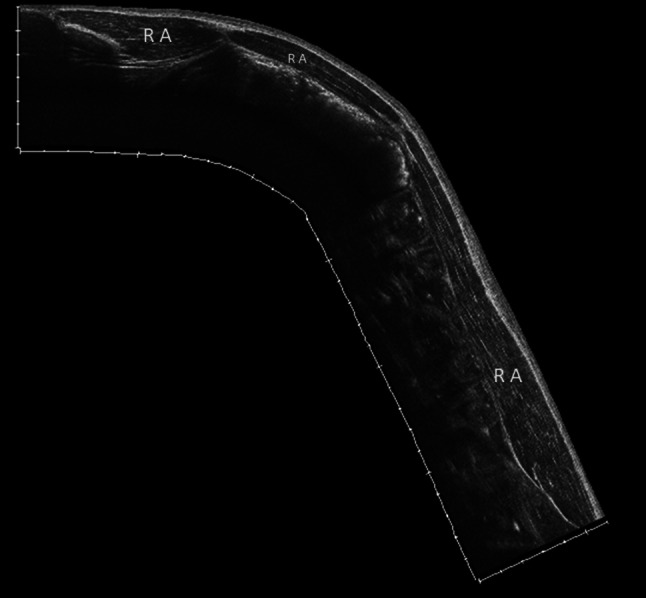

Fig. 2.

Ultrasound panoramic image of the rectus abdominis. The rectus abdominis muscle extends from the last costal cartilage to the upper edge of the pubis. It is composed of several muscular bodies separated by 3 or 4 tendinous intersections